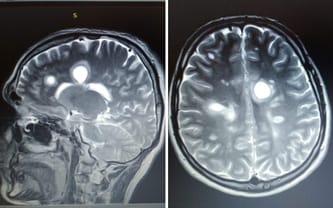

Piętnaście lat temu usłyszałem diagnozę, która na zawsze zmieniła moje życie, stwardnienie rozsiane w postaci rzutowo-remisyjnej. Pamiętam ten dzień bardzo wyraźnie, bo wtedy po raz pierwszy pojawił się strach o przyszłość, sprawność i o to, czy jeszcze kiedykolwiek będę mógł żyć tak jak wcześniej. Od tamtej chwili choroba uderzyła we mnie aż trzynaście razy, a każdy rzut zabierał kolejną część sił, niezależności i pewności jutra.